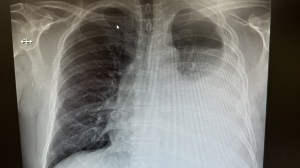

Our 24 Hour X-ray